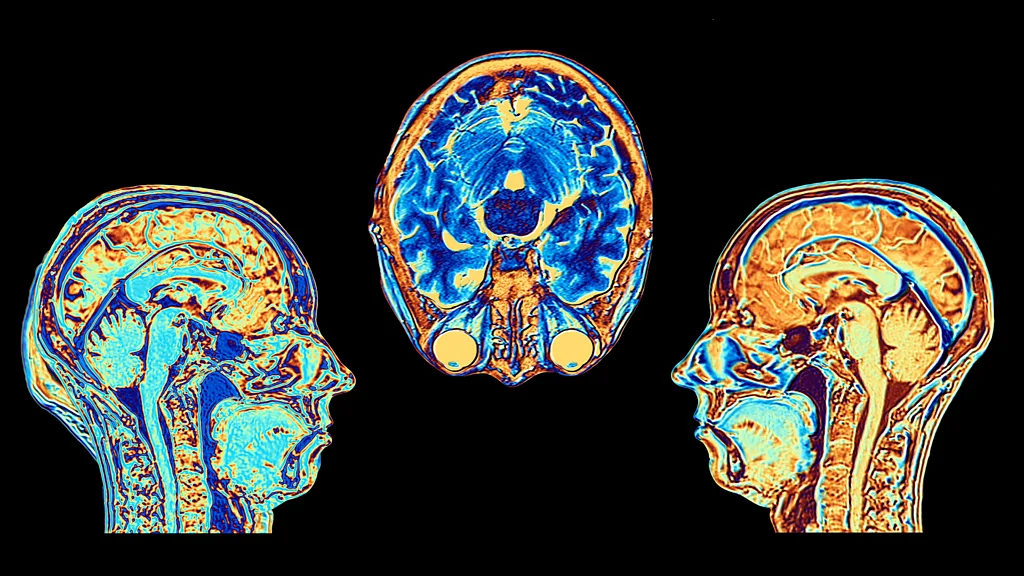

Ideja e një “butoni rregullues mendor” nuk është aq e largët sa mund të duket. Shumica e neuroshkencëtarëve sot bien dakord se zgjimi ynë ekziston në një lloj vazhdimësie. Ai koordinohet nga një rrjet kompleks rajonesh të trurit, në qendër të të cilit gjendet një tufë e vogël neuronale e njohur si “locus coeruleus”, që në latinisht do të thotë “pika blu”.

Përshkrimi është fjalë për fjalë: neuronët në locus coeruleus kanë ngjyrën e safirit për shkak të prodhimit të një neurotransmetuesi të veçantë të quajtur norepinefrinë. Kjo gjithashtu jep një tregues për funksionin e tij, pasi norepinefrina kontrollon gjendjen tonë të eksitimit fiziologjik dhe psikologjik.

Locus coeruleus ndodhet në trungun e trurit, pak mbi pjesën e pasme të qafës dhe përmban rreth 50,000 qeliza, një pjesë fare të vogël krahasuar me 86 miliardë neuronët që ka mesatarisht sistemi nervor qendror. Mjeku i Maria Antonetës, Félix Vicq d’Azyr, ishte i pari që e identifikoi në fund të shekullit të 18-të, por për një kohë të gjatë nuk tërhoqi shumë vëmendje.